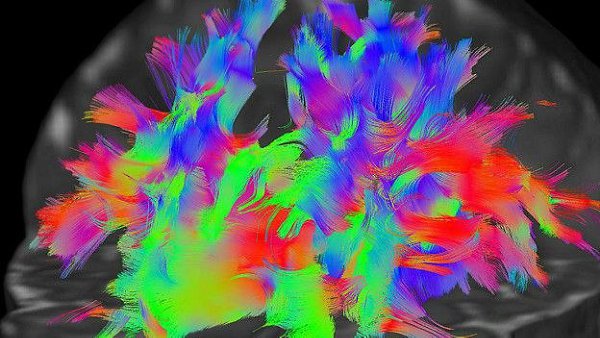

фото 1, 3 - Разные цвета обозначают нервные волокна, идущие в разных направлениях – таким образом ученые выясняют, какие именно проводящие пути связывают различные отделы мозга